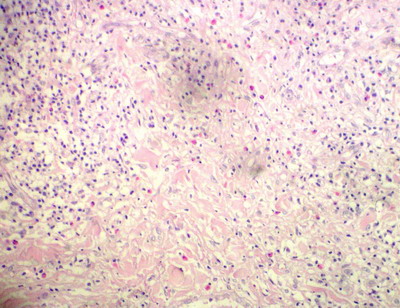

A 4 mm punch biopsy specimen was obtained from the centre of one nodule. Another excision biopsy was taken from the axillary lymph node. H & E stained sections revealed, cutaneous infiltration extended from the middle to lower dermis as well as in the subcutaneous fat. The infiltrate consisted of normal and atypical histiocytes with lymphocyte and plasma cells. The atypical histiocytes display large pleomorphic vesicular nuclei. Some of histiocytes contained in their cytoplasm phagocytes, erythrocytes, nuclear debris and fragment of leucocytes. Few cells showed typical Reed-Sternberg cells which are large histiocytic cell with several nuclei or bilobed nucleus that had a mirror image appearance (Fig.2). Lymph node biopsy showed similar findings (Fig.3).

Fig 3: LN biopsy showed multinucleated tumor cells with abundant cytoplasm [H&E X 160]